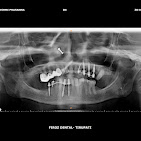

• Dental Implants & Full Mouth Implants: Permanent solutions for missing teeth, including advanced Zygomatic Implants for patients with bone loss.